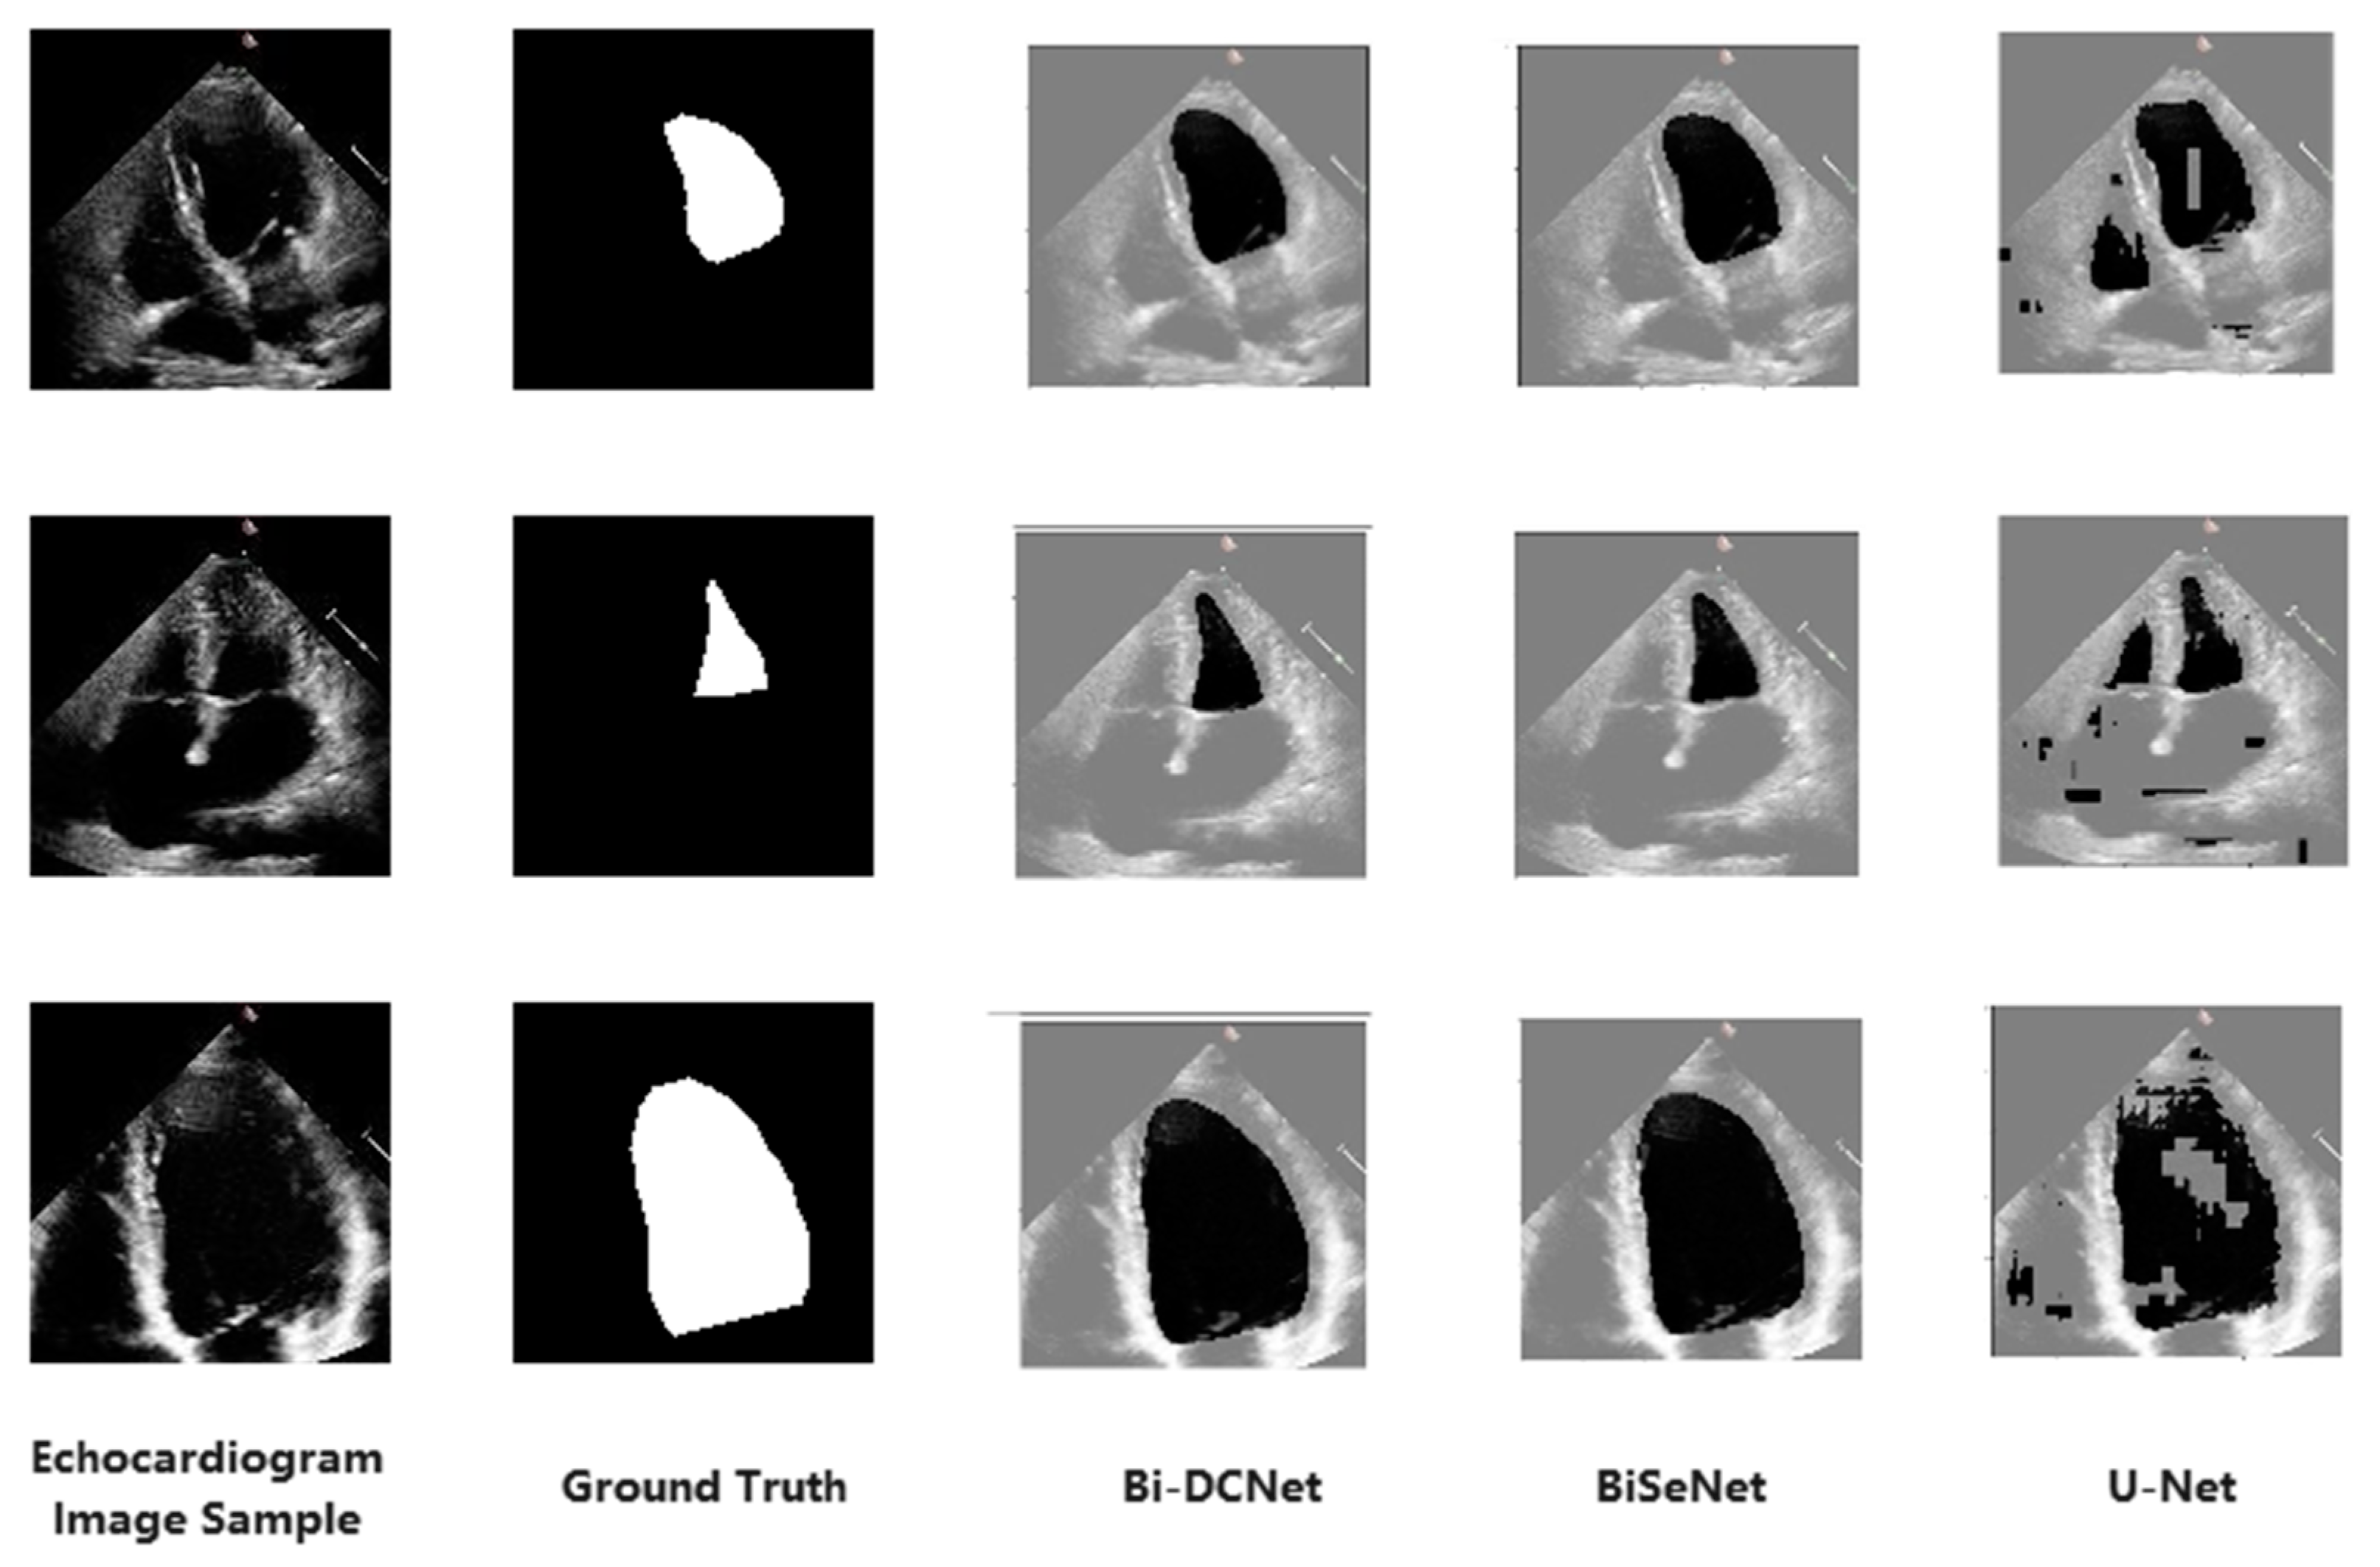

3.2. Visual Results

Figure 4 displays the segmented outputs in visual form for all models. The location of ground truth labels is the leftmost column adjacent to the original echocardiogram images. For the suggested model (Bi-DCNet), BiSeNet, and U-Net, their segmented outputs are also shown in Figure 4’s columns 3, 4, and 5, respectively. Unfortunately, the segmentation accuracy of U-Net is insufficient, primarily because the borderlines are poorly defined, and some background pixels are also included as target objects.

Figure 4.

Visual comparisons of the proposed model to other segmentation models.

However, the Bi-DCNet and BiSeNet borderlines are rather precise. In order to preserve the spatial information of the image and produce a high-resolution feature map, both structures created three convolutional layers with a short step size, using a more significant number of channels and a shallower network. On the other side, channel attention-based ARM selected the discriminative high-level semantic features from the last two steps of the context path. This led to the much better visual results of Bi-DCNet and BiSeNet, illustrating that the bilateral structures had better accuracy regarding left ventricle representation than the U-shaped structure.